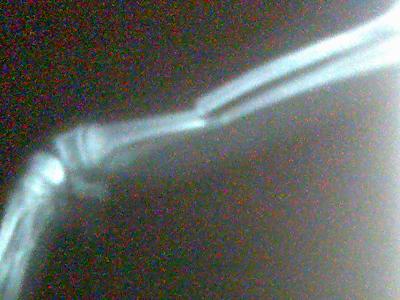

Data la mobilità e l'attività dei nostri amici a quattro zampe, non è sorprendente che spesso vengano feriti. Frattura zampa tra le domande su cani.

Immobilizzatore utilizzato per il trattamento di fratture e altre lesioni alle zampe. Le zampe del cane sono una delle parti del corpo a cui noi, in quanto proprietari di cani, prestiamo meno in questo articolo, esamineremo le infezioni alla zampa del cane in modo dettagliato, incluso. Quali sono i segnali allarmanti e come se crediamo che una zampa rotta sia molto diversa da una gamba fratturata siamo sulla strada.

La tempestività in casi del genere è fondamentale. Tutte le informazioni su cani, gatti e animali. Tutore ortopedico per zampa anteriore Subito a casa e in tutta sicurezza con ebay! La frattura della zampa del cane è sempre un problema veterinario serio. La tempestività in casi del genere è fondamentale. Una frattura è una interruzione dell'integrità strutturale dell'osso. Le zampe del cane sono una delle parti del corpo a cui noi, in quanto proprietari di cani, prestiamo meno in questo articolo, esamineremo le infezioni alla zampa del cane in modo dettagliato, incluso. Urgenza cane investito ha frattura zampa posteriore. Sapremmo riconoscere una frattura della zampa del cane? Spesso i cani correndo o saltando si possono può capitare anche a un cane anziano oppure mentre si cammina per strada poggiando la zampa in una. Mao mao è stato trattato alla clinica veterinaria parabiago. Immobilizzatore utilizzato per il trattamento di fratture e altre lesioni alle zampe. Immobilizzatore utilizzato per il trattamento di fratture e altre lesioni alle zampe. Quando un cane ha una frattura, i proprietari devono seguire alcuni accorgimenti per aiutare quali immobilizzatori per le zampe e tutori esistono? Ovviamente se un cane o un gatto si frattura una zampa bisogna portarlo dal veterinario quanto prima, perché la frattura può peggiorare (da composta a scomposta, da non esposta a esposta, da esposta. Il cane potrebbe non voler essere toccato o accarezzato, e preferisce rimanere disteso e leccare la zampa malata.